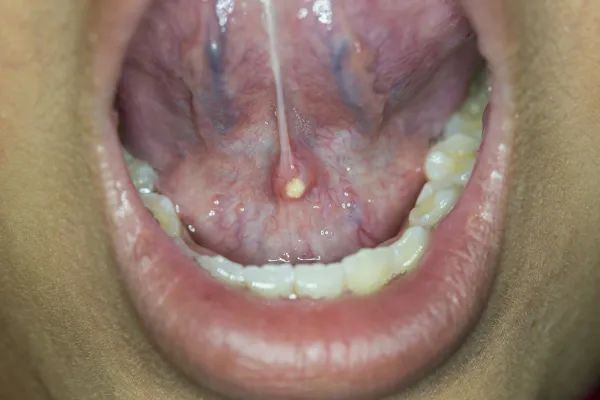

隐藏的口臭来源:扁桃体结石

图片来源:r/gifs@reddit扁桃体结石是扁桃体隐窝中积聚的食物残渣和分泌物逐渐钙化形成的。可能有接近 10% 的人存在扁桃体结石。

多数扁桃体结石是隐秘的存在,并不会带来什么症状,只是偶尔照镜子时被看到,或者在轻咳后咳出一小团臭臭的黄东西。但有些人的扁桃体结石可以导致严重口臭,令人难以忘怀的臭鸡蛋恶臭味儿。

饭后好好漱口,能预防扁桃体结石出现。如果扁桃体已经带来了口臭麻烦,又表浅可见,可以在医生的指导下用棉签、镊子、冲牙器等试试清除。

严重又不好去除的扁桃体结石,医生可以借助手术方式取出,或者是直接进行扁桃体切除术。